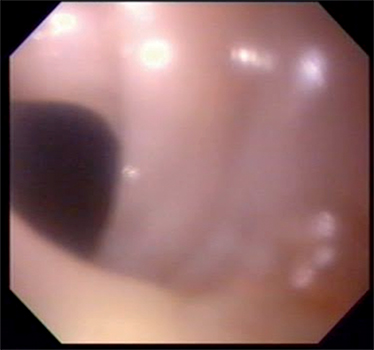

Se efectuó un tránsito esófagogastroduodenal (TEGD) que reveló a nivel esofágico superior la presencia de una ligera membrana que no impedía el pasaje del material de contraste (Figura 3). Se programó la realización de una videoendoscopía digestiva alta (VEDA), objetivándose la presencia de una membrana grisácea en el tercio superior esofágico, la cual ocupaba menos del 25 % de la circunferencia (Figura 4).